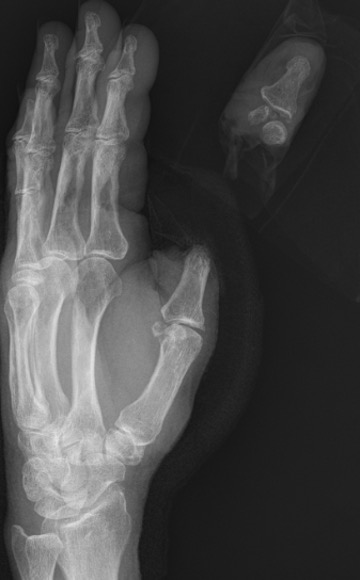

Thumb replant

![]()

Background

Thumb has first priority

A successfully replanted thumb is always better than any reconstruction

- thumb provides 40% of hand function

- a fixed stump / post is very useful

Level

Detipped thumb can be successful

- need dorsal veins in stump

- need 4mm of skin proximal to nail plate

- all efforts should be made to preserve thumb length